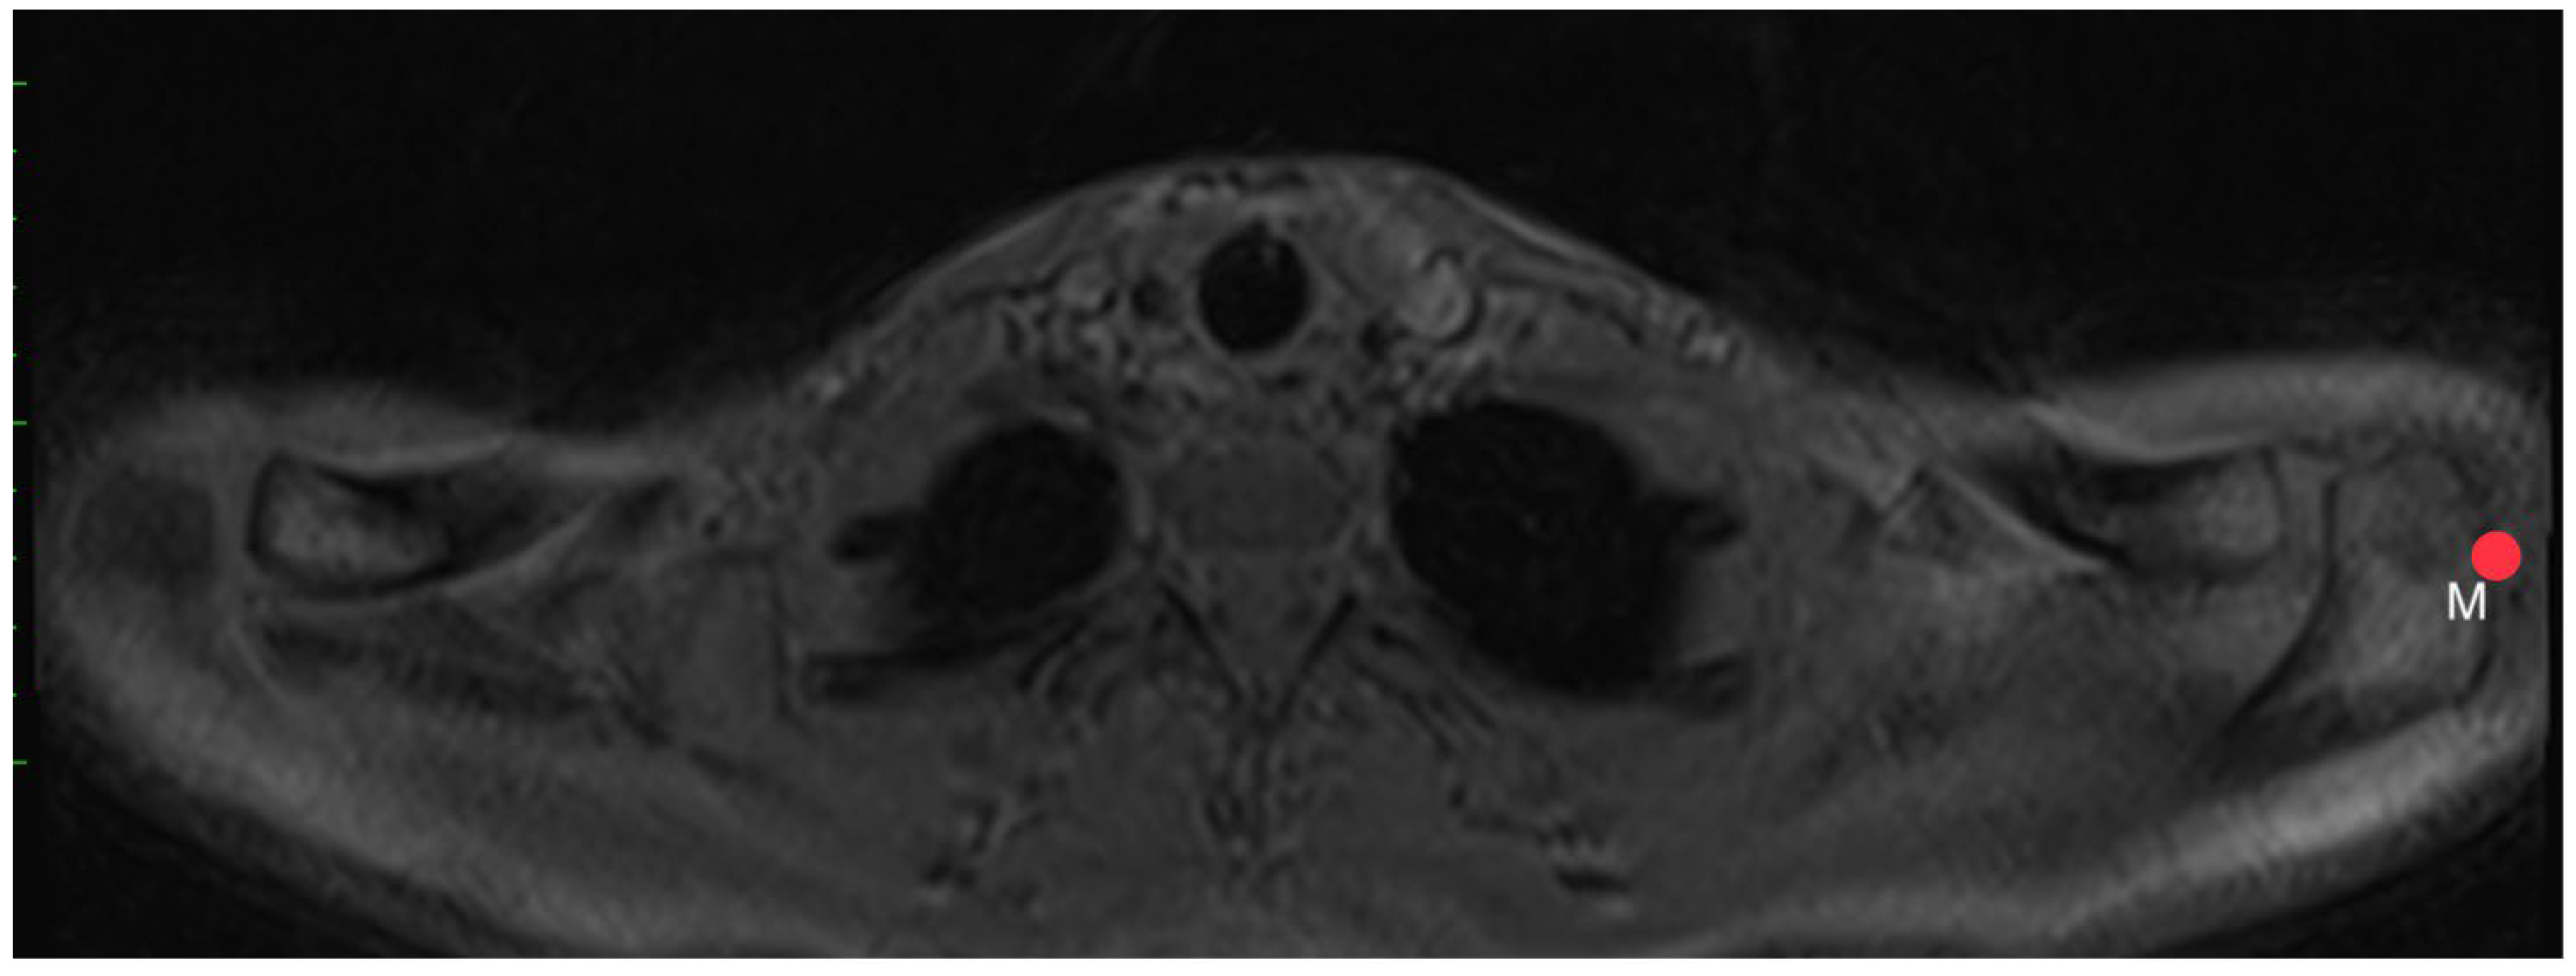

2.3. Acromion Index (Figure 1)